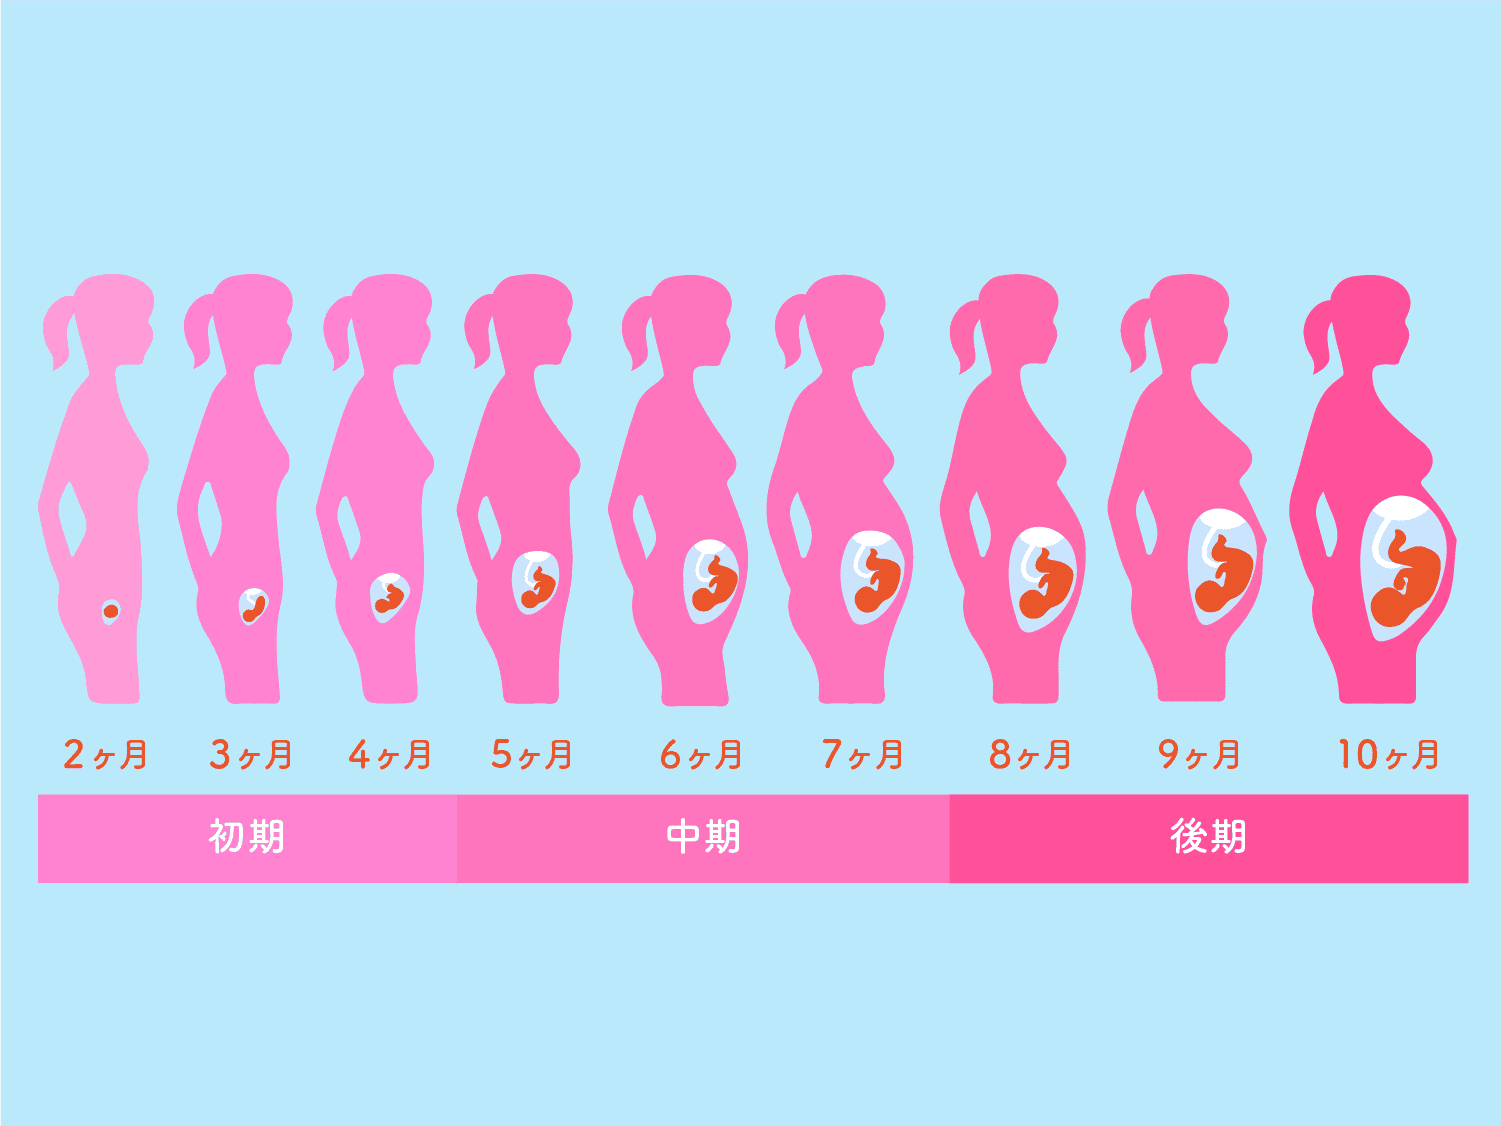

おそらく、定期的に生理が来なくなったときに初めて妊娠に気づくでしょう。ただし、予定日前後に生理の量が非常に少ない場合は、妊娠していないと考えないでください。妊娠の最初の数週間に非常に軽い出血が起こる可能性があります。

- 腫れた腹部

健康な妊娠は 40 週間続きます。妊娠37週未満で出産した赤ちゃんは、

時期尚早。十代の母親たちは、

場合によっては、これらの赤ちゃんは体や脳が完全に発達していないこともあります。赤ちゃんの未熟度によっては、健康や発育に生涯にわたる困難が生じる可能性があります。

最初の6 か月間は、少なくとも月に 1 回は予約を取ることになるでしょう。妊娠の最後の数か月間は隔週で医師の診察を受け、最終月には毎週の診察で終わります。これらの訪問は、あなたとあなたの赤ちゃんが健康であることを確認するために行われます。

診察室では、体重が測られ、血圧が測定され、腹部のサイズが測定されます。赤ちゃんが成長するにつれて、医師は赤ちゃんの位置を感じ、心拍を聞きます。